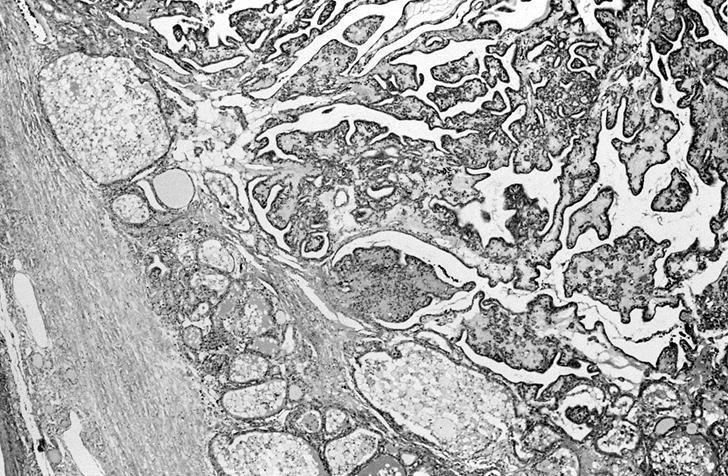

Molecular / cytogenetics description

- PAX8::PPARG fusion (~10%) (Cancer Genet Cytogenet 2010;196:7)

- Clonal cytogenetic abnormalities and copy number variations (~50%) (Cancer Genet Cytogenet 1998;101:42, PLoS Genet 2016;12:e1006239)

Molecular / cytogenetics images

Images hosted on other servers: